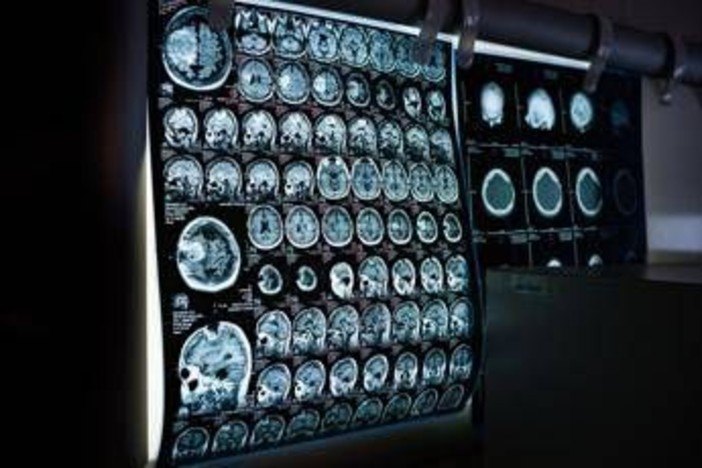

Uno spray nasale testato sui modelli animali potrebbe invertire l'invecchiamento del cervello con sole 2 dosi, riducendo drasticamente l'infiammazione cerebrale, ripristinando le centrali energetiche cellulari del cervello e migliorando così significativamente la memoria. Un processo di ringiovanimento che agirebbe nel giro di poche settimane per durare mesi.

E' il risultato dello studio condotto dai ricercatori della Texas A&M University (Naresh K. Vashisht College of Medicine) negli Stati Uniti. Lo spray contiene minuscole particelle biologiche note come vescicole extracellulari (Ev), che agiscono come veicoli di consegna con a bordo un potente carico genetico, i microRna. Le sostanze aggirano lo scudo protettivo del cervello e viaggiano direttamente nel tessuto cerebrale, dove vengono assorbite. Arrivati a destinazione nelle cellule immunitarie residenti nel cervello, i microRna 'spengono' i sistemi noti per essere responsabili dell'infiammazione cronica nel cervello che invecchia.

Per spiegare il senso di questo processo, gli scienziati invitano a immaginare il cervello come un motore ad alte prestazioni: nel corso dei decenni questo motore non solo si usura, ma inizia anche a surriscaldarsi. Piccoli 'focolai' di infiammazione covano nelle profondità del centro della memoria, creando una persistente nebbia mentale (brain fog) che rende più difficile pensare, formare nuovi ricordi o persino adattarsi a nuovi ambienti, aumentando al contempo il rischio di disturbi come il morbo di Alzheimer. Questo processo a lenta combustione viene chiamato neuroinfiammazione. E per decenni si è pensato che fosse il prezzo inevitabile dell'invecchiamento. Ma il nuovo studio, pubblicato sul 'Journal of Extracellular Vesicles', suggerisce che l'ondata infiammatoria potrebbe essere reversibile.

Il team guidato da Ashok Shetty, distinguished professor dell'ateneo e associate director dell'Istituto di medicina rigenerativa, insieme ai ricercatori senior Madhu Leelavathi Narayana e Maheedhar Kodali, ha sviluppato lo spray nasale e ha verificato che a livello cellulare il trattamento ha ricaricato i mitocondri neuronali, ovvero le centrali energetiche che si trovano all'interno delle cellule cerebrali. La terapia ha dissipato la nebbia mentale e ha anche migliorato fisicamente la capacità del cervello di elaborare e immagazzinare informazioni.